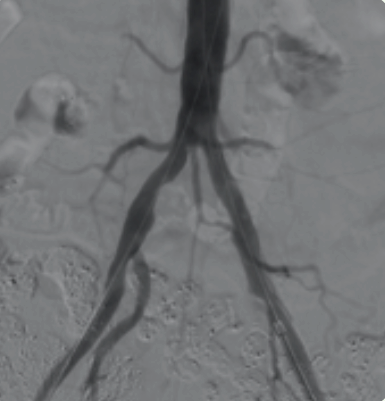

Using imaging for guidance, a catheter is thread through the blocked artery in the legs. Once there, a device is used to remove the calcifications or plaque that is narrowing the arteries. At VSNC there are several different devices used, depending on the size shape or make up of the narrowing. This is a minimally invasive treatment that does not require surgery, just a small nick in the skin.